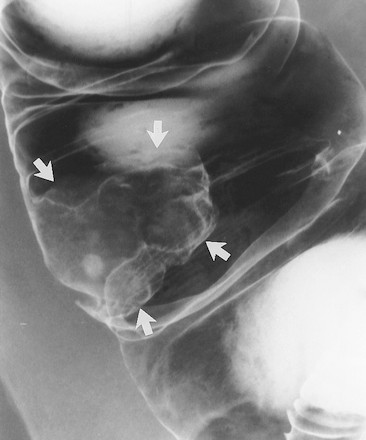

Ung thư biểu mô hình khuyên hay phát triển ở vùng sigma nhất nhưng cũng có thể thấy ở đại tràng xuống, đại tràng ngang, và đại tràng lên. Trái lại, chúng không xảy ra ở manh tràng và trực tràng do khẩu kính của các đoạn đó lớn. Các tổn thương hình khuyên biểu hiện trên phim cản quang baryt bằng hẹp chu vi lòng ruột, với sự phá hủy niêm mạc, với các bờ nhô lên như dải đá ngầm (Hình 11, 12). Chủ yếu phải quan sát các quai ruột tách nhau, nếu quai ruột chồng nhau có thể không quan sát thấy tổn thương (Hình 12).

Hình 11. Hình cản quang kép khu trú, bệnh nhân nằm ngửa phát hiện hai ung thư biểu mô tuyến đồng thời. Khối ung thư biểu mô hình khuyên ở đoạn cuối đại tràng ngang đặc trưng bởi sự phá hủy niêm mạc và các bờ nhô lên hình đá ngầm (mũi tên trắng, thẳng). Khối ung thư biểu mô tuyến thứ hai dạng polyp (mũi tên đen) nằm ở đoạn đầu đại tràng ngang. Bệnh nhân này cũng có một polyp tuyến (mũi tên trắng, cong) ở sát bờ ngoài tổn thương hình khuyên.